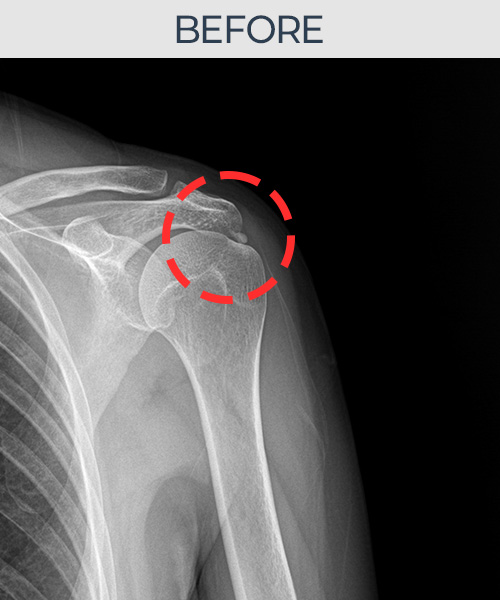

비수술 치료 전후사진

수천건의 수술 경험을 바탕으로 정확히 진단하여

인대파열을 비수술로 치료합니다.

수술을 해야만 재건이 가능한 인대파열도 있습니다.

플래티넘정형외과에서는 수술이 필요없는 인대파열만을

정확히 진단하여 특허받은 술기로 비수술로 치료합니다.